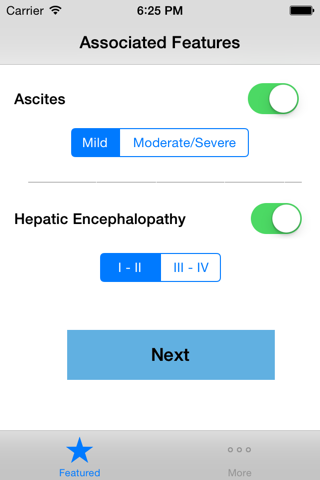

Child-Pugh (CP) classification was originally designed to determine the risk of portocaval shunt surgery in cirrhotic patients. CP classification provides mortality risk with abdominal surgery, survival rates and a likelihood of developing complications secondary to underlying cirrhosis. The input variables include serum bilirubin, serum albumin, presence of ascites or encephalopathy and prothrombin time. The minimum CP score is 5 whereas the maximum possible score is 15. A score of 5-6 is classified as class A indicating well compensated cirrhosis, whereas a score of 7-9 is class B with significant functional compromise, and a score of 10-15 is a class C with decompensated cirrhosis. This application implements the CP classification system and assigns a score and stage based on the user provided input.